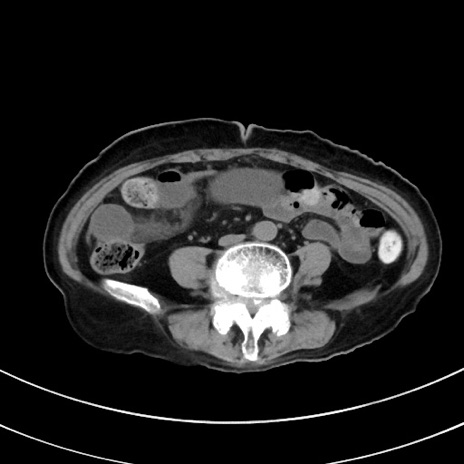

症例33(横断像)

【症例】70歳代 女性

【主訴】心窩部痛

【現病歴】延髄病変の精査・加療にて神経内科入院中。本日より心窩部痛あり。

【既往歴】虫垂炎

【身体所見】右下腹部を中心に圧痛と反跳痛あり。

【データ】WBC 10900、CRP 0.02